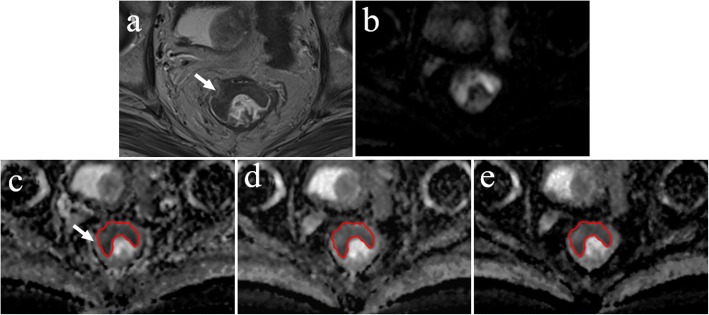

Each region of interest (ROI) with a maximum cross-sectional tumour size was outlined on the ADC map so that the T2 shine-through effect could be effectively avoided, which is helpful for displaying clear border between the tumour and normal tissue [19]. Additionally, DWI and T2W images were used as a reference to delineate the tumour on ADC images (Fig. 1). The mean ADC values of the lesions were measured using the single-slice ROI method, which is briefly described in the following steps: select the maximum slice of the lesion, delineate the entire range of the lesion, measure three times and then calculate the average [19–21]. In addition, the areas of ROI were also recorded.

Fig. 1.

Example images for delineating ROI of rectal lesion. a T2W image. b Diffusion-weighted image at b = 1000 s/mm2. c ADC map derived from a b-value combination of 0, 1000 s/mm2. d ADC map derived from a b-value combination of 100, 1000, 1500 s/mm2. e ADC map derived from a b-value combination of 500, 1500, 2000 s/mm2